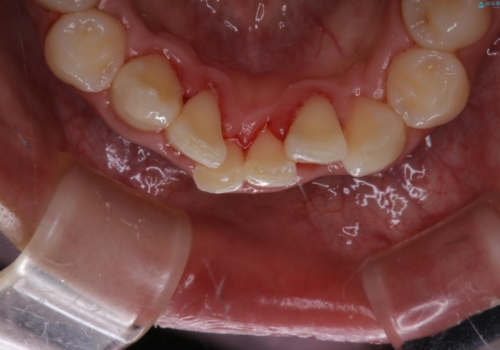

矯正を始めるのをきっかけにクリーニングを約5年ぶりに行ったそう。

プラークや歯石がとても多く付いていたので、すべて除去していきました。

長い間、歯石やプラークが付いていたため、歯茎が腫れて出血していますが、汚れを除去したことによってだんだんと腫れが引いてきます。再度、汚れが付かないようにホームケアを頑張ることがとても大切なため、ブラッシングの説明も細かくさせていただきました。